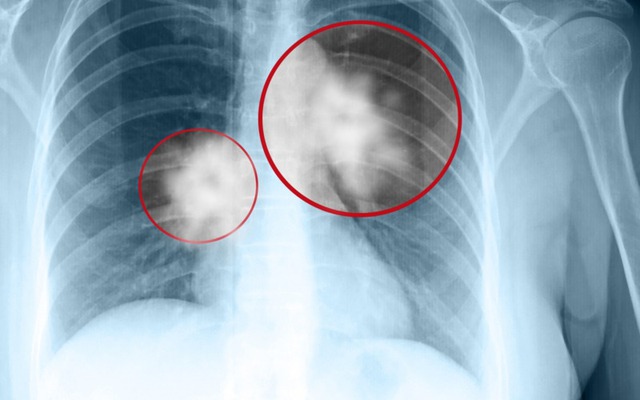

Anh Wang nhìn vào những nốt kính mờ trên phim chụp mà lòng như lửa đốt. Anh không giữ được bình tĩnh, suýt chút nữa thì làm loạn cả bệnh viện đòi phẫu thuật cho con. Đến khi được bác sĩ từ tốn giải thích kỹ, anh mới vỡ lẽ. Vừa ôm con trai khóc trong vui mừng, vừa rối rít xin lỗi đội ngũ y bác sĩ.

Sự mâu thuẫn này thực chất dựa trên những chỉ số y khoa rất cụ thể. Khối u của bé Xiao Chen chỉ rộng 8 milimét, là dạng kính mờ thuần túy, không có hàm lượng chất rắn.

Bác sĩ giải thích rằng, Tổ chức Y tế Thế giới đã loại loại tổn thương này khỏi danh sách u ác tính xâm lấn và coi đây chỉ là tổn thương tiền ung thư hoặc lành tính dựa trên loại nốt. Ngay cả trong số các nốt ác tính, hầu hết là ung thư phổi "lành tính" hoặc giai đoạn rất sớm với tiên lượng tốt. Chúng có tốc độ phát triển cực chậm, có khi mất hàng chục năm vẫn đứng yên, hầu như không đe dọa đến tính mạng.

- Kích thước nốt mờ tăng nhanh vượt mức 1cm.

- Nốt mờ xuất hiện phần đặc bên trong (chuyển sang dạng hỗn hợp).

- Bờ nốt mờ không còn mịn mà có hình răng cưa hoặc tua gai.

Nếu không có các dấu hiệu này, gia đình chỉ cần theo dõi định kỳ.